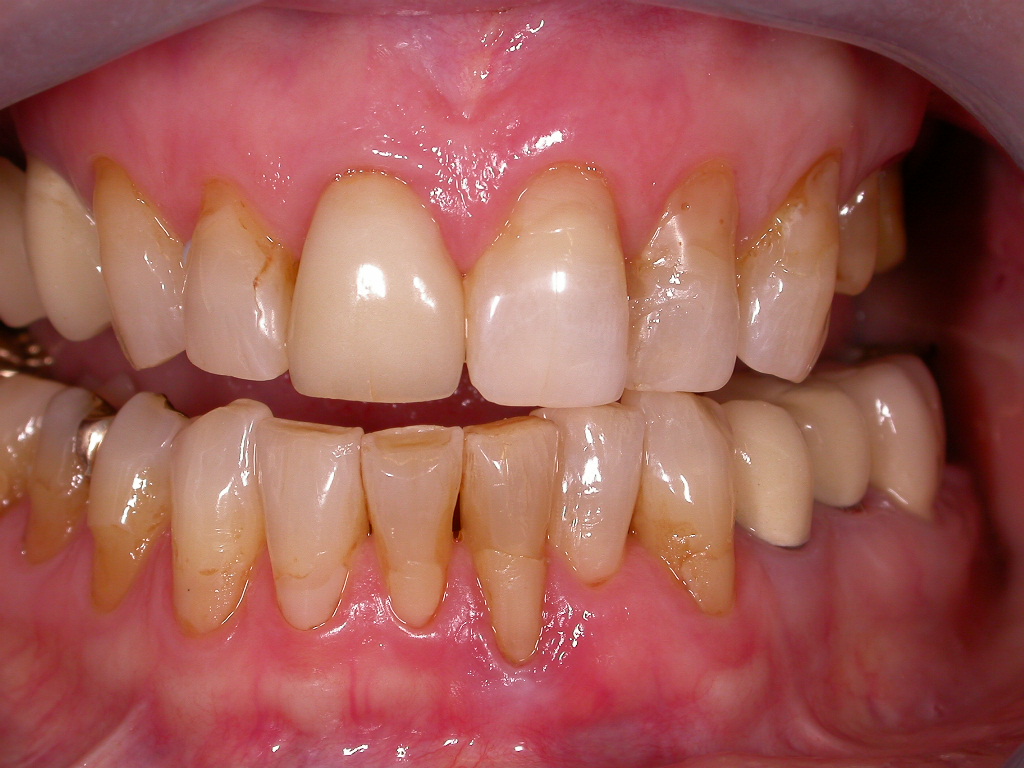

Sehr unzufriedener Patient, der immer wieder Reparaturen mit Kunststoff und einzelnen Kronen bei seinem langjährigen Zahnarzt bekommen hat

Vorher: Sehr unzufriedener Patient, der immer wieder Reparaturen mit Kunststoff und einzelnen Kronen bei seinem langjährigen Zahnarzt bekommen hat

Kompletterneuerung mit vollkeramischen Veneers und Kronen; vorher Endo-Revisionen unter dem Mikroskop und PAR-Behandlung; Entfernung der Weisheitszähne in unserer Praxis

Nachher: Kompletterneuerung mit vollkeramischen Veneers und Kronen; vorher Endo-Revisionen unter dem Mikroskop und PAR-Behandlung; Entfernung der Weisheitszähne in unserer Praxis